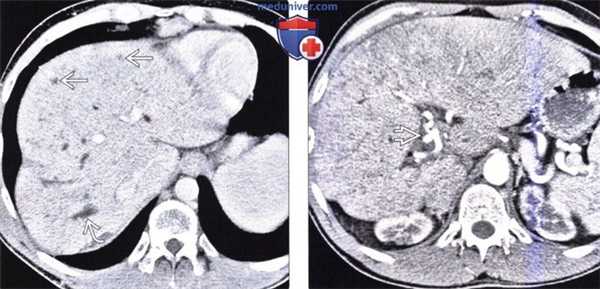

(Слева) На аксиальной КТ с контрастным усилением определяется в значительной степени уменьшенный в размерах медиальный сегмент печени, расположенный между щелью серповидной связки и желчным пузырем. Передние сегменты также уменьшены в размерах.

(Справа) На аксиальной КТ с контрастным усилением в этом же случае визуализируются толстая кишка и жировая клетчатка сальника, заполняющие промежуток между правой и левой долей печени у пациента с врожденной гипоплазией переднего и медиального сегментов.

(Слева) На аксиальной КТ с контрастным усилением определяется гипоплазия переднего и медиального сегментов. Обратите внимание на клипсу после ранее выполненной холецистэктомии (в норме желчный пузырь располагается между долями печени). Также обратите внимание на грыжевое выпячивание желудка и толстой кишки латерально и в краниальную сторону.

(Справа) На более каудальном аксиальном КТ срезе без контрастного усиления у этого же пациента визуализируется свободное пространство, обусловленное врожденной гипоплазией переднего и медиального сегментов печени, заполненное жировой клетчаткой сальника и печеночным изгибом ободочной кишки.